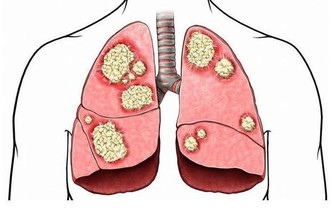

在中醫理論中,造成水腫的原因很多,除了器質性病變(例如腎臟病、心臟病等)之外,肺、脾、腎等3個臟腑功能失調,都容易引發水腫,治療上需辯證論治,視個人體質和症狀表現再對症下藥,量身處方才能有效消除水腫,擺脫虛胖,變得健康又美麗。